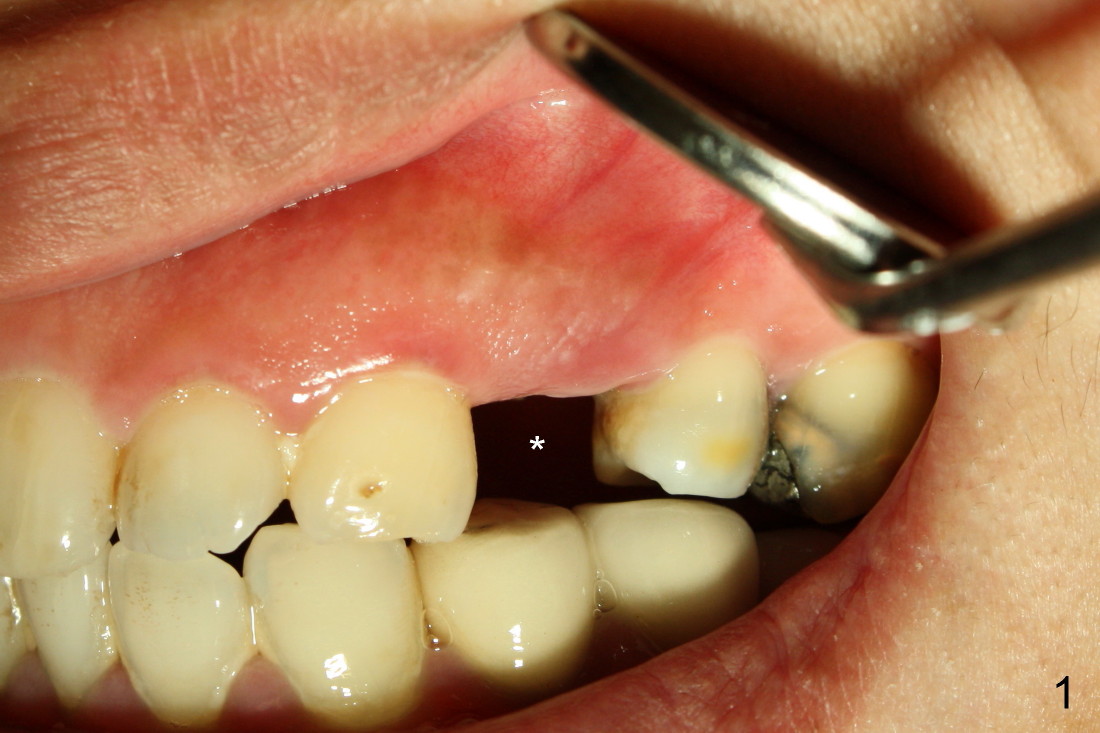

The second patient who is going to have an immediate implant in the upper bicuspid region is a 41-year-old lady. She is extremely scared of dental treatment. The second challenge is a periapical lesion associated with residual roots (Fig.1,2,4, as compared to freshly fractured tooth in the first case).

The closure of the socket involves raising and advancing both buccal and lingual flaps (Fig.10,11). When a crown is cemented, the patient is not pleased with recessive papillae (Fig.12 (arrowheads),13). It appears that flaps should be avoided to prevent cosmetic issue. Immediate implant is not enough for cosmetics; immediate provisional can close the extraction socket and support the papillae.